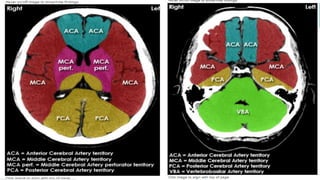

Blood supply